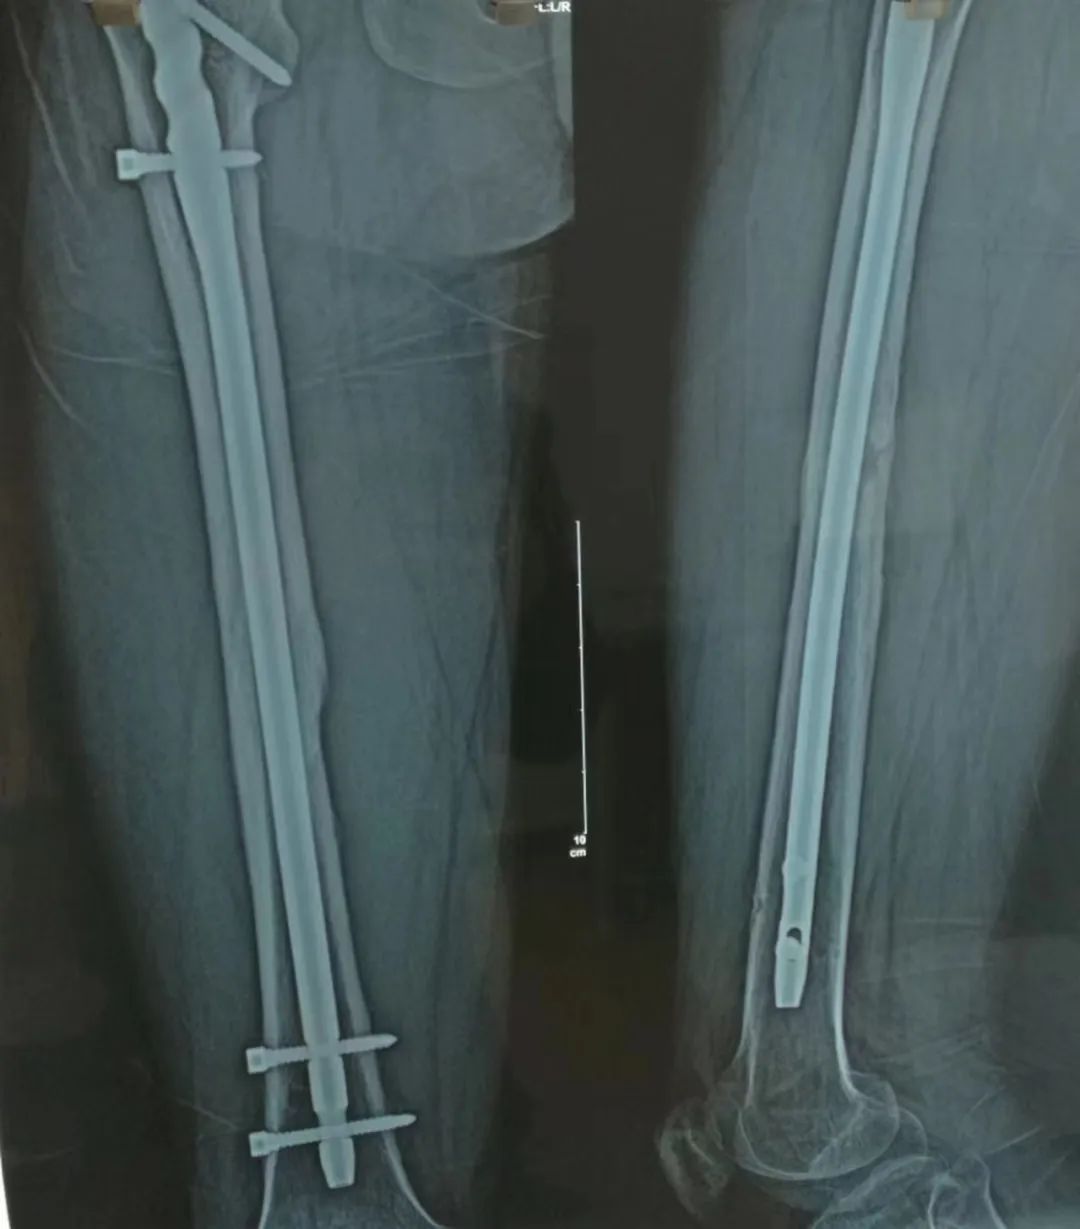

被诊断为大腿外侧粉碎性骨折

腿内的钢针

直至8年后才被全部取出

小张大腿内部的钢针。